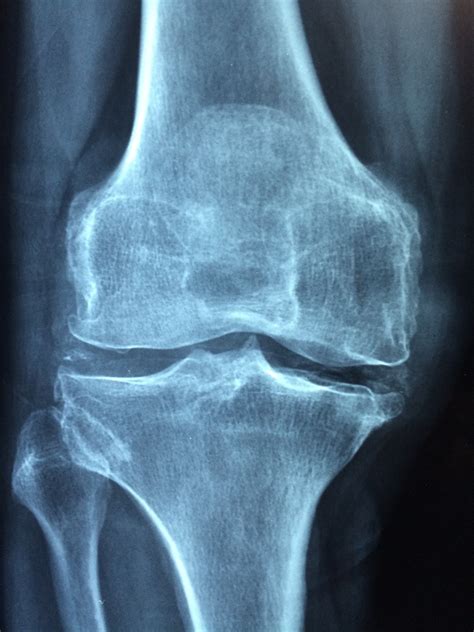

Joint Care Capsule: Ayurvedic Relief for Joint Pain & Inflammation